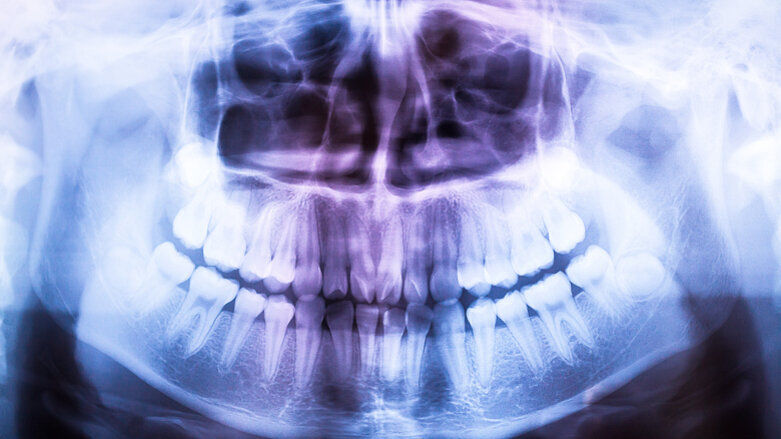

YORK, VK – Röntgenfoto’s zijn nuttig bij het stellen van een diagnose, maar het nadeel ervan is dat de patiënt wordt blootgesteld aan potentieel schadelijke straling. Een tandarts zou dus bij elke röntgenfoto die hij maakt de voor- en nadelen voor de patiënt tegen elkaar af moeten wegen. Onderzoekers van de Universiteit van York ontdekten echter dat tandartsen vaker kiezen voor een röntgenfoto wanneer ze per gemaakte foto betaald worden. Ook wanneer het klinisch niet noodzakelijk is.

Wanneer patiënten vrijgesteld waren van kosten, steeg het aantal röntgenfoto’s eveneens significant. Er werden minder röntgenfoto’s gemaakt door tandartsen met een vast salaris, zo beschrijft het artikel De uitgebreide analyse van het Centre for Health Economics van de Universiteit van York bekeek data afkomstig van tandartsen aangesloten bij de National Health Service (NHS), die ofwel in loondienst waren, ofwel een honorarium ontvingen per handeling. Data uit een periode van ruim een decennium werden in het onderzoek meegenomen en meer dan een miljoen behandelingen werden in het onderzoek geïncludeerd. Het onderzoek bevestigt eerder, maar beperkt, onderzoek naar hoe beloningsschema’s van tandartsen invloed kunnen hebben op de intensiteit van behandeling en de prevalentie van controles.

“Onze resultaten tonen aan dat de methode van vergoeding voor een tandarts een significante invloed heeft op het gebruik van röntgen. Tandartsen die een aparte vergoeding krijgen voor elke röntgenfoto, maken er meer,” stellen de onderzoekers in hun paper.

Ondanks dat zij verder onderzoek aanmoedigen, zeggen de onderzoekers dat hun bevindingen nu al een significante betekenis kunnen hebben voor beleid voor volksgezondheid, in het bijzonder als het gaat om het beschermen van patiënten tegen overmatige blootstelling aan röntgenstraling.

“Zelfs al zouden patiënten er vrijwillig voor kiezen om een lager aantal röntgenfoto’s te krijgen dan optimaal is na het afwegen van de risico’s en de voordelen, dan nog lijkt het vanuit ethisch perspectief discutabel dat het aantal röntgenfoto’s dat een verzekerde patiënt krijgt, significant hoger is bij tandartsen die per handeling worden betaald, dan bij tandartsen in loondienst,” concluderen de wetenschappers. “Dit betekent dat patiënten behandeld door een tandarts in loondienst mogelijk minder röntgenfoto’s krijgen dan optimaal is voor hun mondgezondheid, of dat verzekerde patiënten behandeld door een tandarts die per behandeling betaald wordt, er te veel krijgen.”

Het onderzoek, getiteld ‘First do no harm—The impact of financial incentives on dental X-rays’, is in maart 2018 verschenen in het wetenschappelijke tijdschrift Journal of Health Economics.